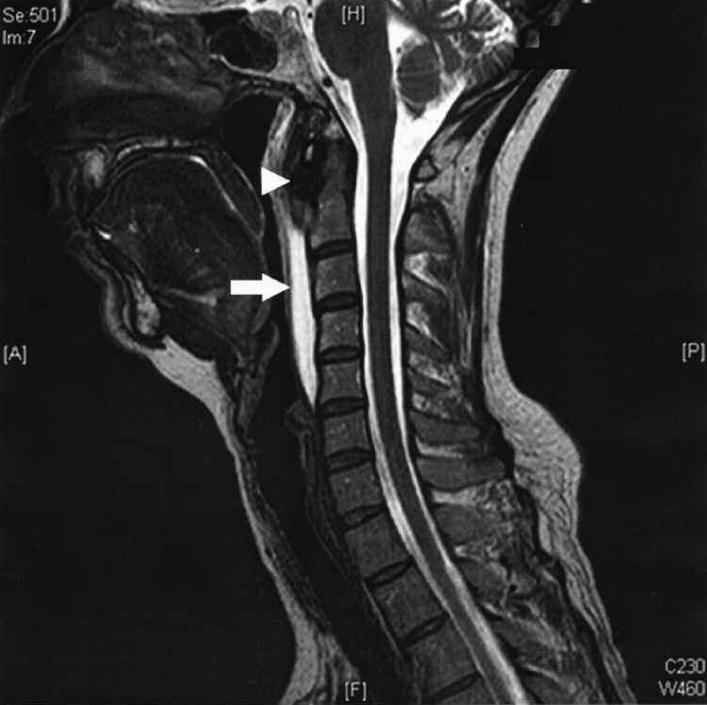

明确诊断主要通过影像学方法,颈椎CT是关键。 颈长肌钙化性肌腱炎特异性的影像表现是C1-4椎体前缘软组织肿胀和积液与C1椎体前弓下方不规则钙化沉着共存。

图:椎前积液

图:椎前积液和C1椎体前弓下方不规则钙化沉着

CT的高分辨率能够明确肌腱内的钙化,能够明确是钙化而不是其他骨骼来源的高密度影。 钙化一般位于寰椎前弓的下方和枢椎齿状突的前方,少部分可位于下颈椎前侧 。CT有助于明确椎体前积液的存在和排除其他病理表现,如骨折或脓肿。MRI对诊断不是必须,但有时可帮助确定软组织异常,排除咽后脓肿,脊椎炎或肿瘤。 MRI检查T2加权在椎前可见局限性的裂隙样区域,大多位于C1-4水平,呈高信号改变,这反应是由于炎症引起的积液 。T2加权、脂肪抑制序列和T1加权对鉴别积液和脂肪组织、含脂肪的骨髓以及咽后感染、脊椎炎有重要作用。MRI检查在钙化检查方面存在不足,T2加权呈低信号。